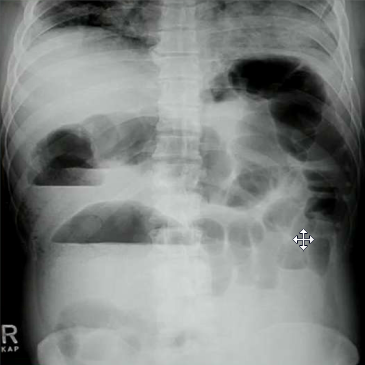

What does this patient have?

Ascities. Note increased density, central bowel loops, thickened peritoneal fat stripe, loss of other edges (liver, spleen and bladder)